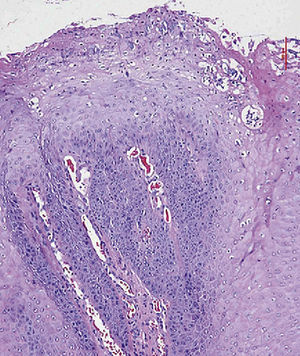

La imagen histológica muestra una proliferación epitelial marcada con crestas epidérmicas ensanchadas y papilomatosis que penetran profun-damente en el tejido conectivo. En la superficie se observan una tendencia evidente a la queratinización y una coilocitosis (tinción de HE, 10 aumentos).

Desde el punto de vista histológico destaca la formación de prolongaciones digitiformes cuyos extremos aparecen queratinizados. La estratificación epitelial está conservada y, en ocasiones, pueden aparecer mitosis. Las atipias epiteliales son raras. Los VPH se pueden identificar con métodos inmunocitoquímicos o mediante la técnica de hibridación in situ8.